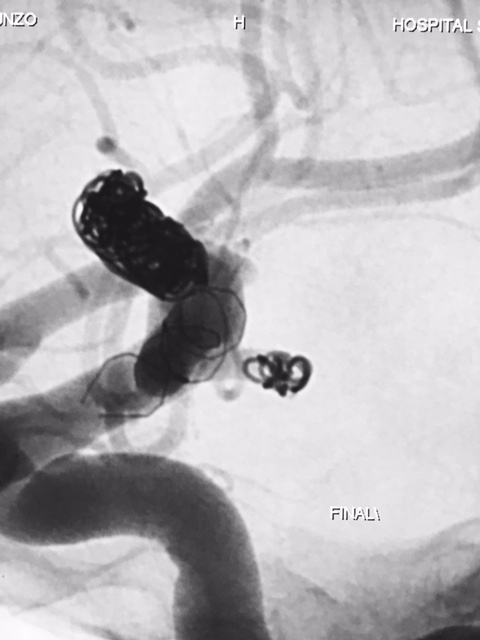

Ambos posicionados em segmento proximal de artéria carótida interna, com progressão gradativa no Cateter Envoy XB DA 070 para segmento petroso desta mesma artéria. Inicialmente realizou micronavegação  do  aneurisma de segmento comunicantecateter com microcateter Echelon 10 microguia Silver Speed 0,10  e liberado 2 microespiras  posteriormente progredindo até saco aneurismático do aneurisma de topo de carótida. Assim, em sistema coaxial foi progredido microcateter VASCO 21 até o segmento M1 da artéria cerebral média, sendo optado pela orientação do aneurisma e orientação de seu colo com maior envolvimento deste mesmo vaso. Assim, diante do posicionamento adequado de ambos os microcateteres iniciou a liberação controlado do stent LEO, e por seguinte liberado um total de 8 microespiras no saco aneurismático até oclusão completa-Raymond 1.